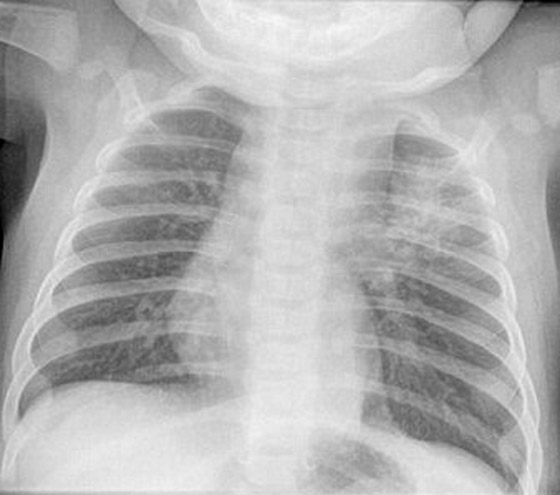

يعاني طفل من حالة مرضية مميتة وهي وجود 20 نوع من الاورام المختلفة في كل انحاء جسده وبداخل أعضائه الداخلية، ويصاب بهذه الحالة شخص واحد من بين 500 شخص في العالم. ايثان موس الذي يبلغ من العمر عامين فقط، تم تشخيص حالته في عمر التسعة أشهر وتبين اصابته بالمرض، حيث بدأت الاورام تكبر وتتكاثر في جميع انحاء جسمه.